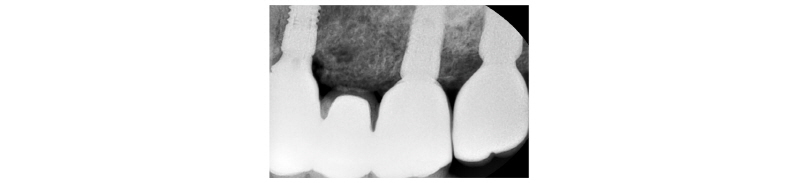

70세의 여자환자로 상악에 사용하던 부분틀니가 불편하다고 호소하시며 내원하였다. 부분 틀니의 지대치인 상악 좌측 견치 또한 보철물 하방으로 우식이 진행되어 보철물 제거후 우식치료 후 보철물을 재제작하여 장착하기로 계획하였다. 치아가 결손되어 있던 상악 좌측 소구치와 대구치 부위는 임플란트 식립(#24i-26i, 27i)을 통한 고정성 보철물 수복을 계획하였다(Fig. 19). 장기간의 부분틀니 장착으로 인해 임플란트 식립 예정 부위의 심한 치조제 흡수가 관찰되었으며 특히 소구치 부위가 가장 흡수 정도가 심하였다(Fig. 20). 전층판막 형성 후 상악 좌측 제 1 소구치 부위는 치조정에서 약 2 mm 정도의 매우 좁은 치조제 폭경이 확인되었다(Fig. 21). 먼저 상악 좌측 제 1 소구치 부위 치조정에 horizontal intraosseous groove를 작게 형성한 후 협측골에 근, 원심 양측에 vertical intraosseous groove를 형성하였다(Fig. 22). Chisel을 이용하여 협측 골판을 조금 확장시킨 다음 spreader drill (RS kit, Dentium, Korea)을 단계적으로 이용하여 충분히 확장시켜 임플란트 식립을 위한 공간을 확보하였다(Fig. 23). 분리된 협,설측 골판 사이 공간으로 Ø4.3 × 10 mm (Implantium, Dentium, Korea) 임플란트를 식립하였다(Fig. 24). 상악 좌측 대구치 부위는 상악동 거상술(측방접근법)을 시행하여 #26i, 27i : Ø4.3 × 10 mm, Ø4.8 × 10 mm (Implantium, Dentium, Korea)를 식립하였다(Fig. 25). 식립된 24i 임플란트와 협,설측 골판 사이의 gap에 합성골 (Osteon II, Xenoss, Korea)을 적용한 다음 협측 골판 상방에 콜라겐함유 합성골(Osteon II Collagen, Xenoss, Korea)을 추가적으로 적용하였고 식립된 26i, 27i 임플란트 부위의 협측골 두께가 얇아서 협측골 상방에도 콜라겐함유 합성골(Osteon II Collagen, Xenoss, Korea)을 적용하였다(Fig. 26). 골이식재 상방에 흡수성 교원질 차폐막(Collagen, Xenoss, Korea)을 피개한 후 감장절개를 통해 장력없이 봉합하였다(Fig. 27, 28). 약 10일 후 발사 시의 임상소견으로 정상적으로 치유가 잘 진행되었다(Fig. 29). 술 후 파노라마 방사선 소견으로 치조제 분할술을 통해 식립된 24i 임플란트와 상악동 거상술(측방접근법)을 시행하여 식립된 26i, 27i 임플란트가 확인되었다(Fig. 30). 4개월 치유 후 이차 수술 시 전층 판막거상 후 협측으로 충분히 증가된 치조제 폭경과 식립된 임플란트 주위에 이식한 골이 혼화되어 치유된 양상이 확인되었고 치유지대주를 연결하였다(Fig. 31). 이차 수술 후 치유가 정상적으로 진행되어 통법에 따라 보철 수복하였다. 보철물 수복 직후 방사선 사진 소견으로 식립된 24i 임플란트의 변연골 위치가 확인되었다(Fig. 32). 보철물 장착 후 1년 후 방사선 소견에서 임플란트 주위 변연골이 안정적으로 잘 유지되고 있었다(Fig. 33). 보철물 장착 4년 후 follow- up 결과 임플란트 주위 치은이 약간 퇴축된 양상을 보였으나 임상적으로 특이한 소견이 관찰되지 않았고 방사선 소견에서 임플란트 주위 변연골이 안정적으로 잘 유지되고 있음을 확인하였다(Fig. 34-36).